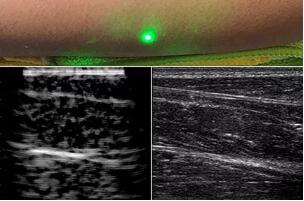

臨床應(yīng)用的無(wú)創(chuàng)超聲,要求探頭與人體皮膚直接接觸來(lái)向身體傳導(dǎo)高頻振動(dòng)的超聲波。但是,有一些特定的患者卻在超聲檢查時(shí)受到限制,比如兒童、燒傷患者和敏感皮膚患者等。而近日麻省理工學(xué)院的研究人員證明,確實(shí)有可能使用激光在不接觸皮膚的前提下對(duì)患者進(jìn)行超聲波掃描。

而麻省理工學(xué)院的研究小組現(xiàn)在開發(fā)了一種使用激光檢測(cè)皮膚上超聲波振動(dòng)的方法,以便可以使用一種激光使皮膚產(chǎn)生共振,而另一種則可以檢測(cè)到振動(dòng),從而達(dá)到“遠(yuǎn)程超聲掃描”的作用。

目前,研究人員已經(jīng)與健康的志愿者測(cè)試了他們的系統(tǒng):從半米遠(yuǎn)處掃描了他們的前臂,并將這些結(jié)果與傳統(tǒng)超聲的結(jié)果進(jìn)行了比較。他們能夠觀察到深達(dá)6厘米的組織,并能看到肌肉,脂肪和骨頭,并報(bào)告其結(jié)果可與標(biāo)準(zhǔn)超聲相媲美。

研究人員用一種激光裝置測(cè)試了這個(gè)想法,該裝置使用一個(gè)波長(zhǎng)為1,550納米的脈沖激光來(lái)產(chǎn)生聲波,并使用第二個(gè)連續(xù)激光,調(diào)諧到相同的波長(zhǎng)以遠(yuǎn)程檢測(cè)反射的聲波。第二個(gè)激光器是靈敏的運(yùn)動(dòng)檢測(cè)器,可測(cè)量聲波從肌肉,脂肪和其他組織反射回來(lái)而引起的皮膚表面振動(dòng)。反射的聲波產(chǎn)生的皮膚表面運(yùn)動(dòng)會(huì)導(dǎo)致激光頻率發(fā)生變化,這種變化可以測(cè)量。通過(guò)機(jī)械掃描人體上的激光,科學(xué)家可以獲取不同位置的數(shù)據(jù)并生成該區(qū)域的圖像。